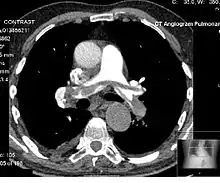

Angiography

Computed tomography angiography (CTA) is a type of contrast CT to visualize the arteries and veins throughout the body.[45] This ranges from arteries serving the brain to those bringing blood to the lungs, kidneys, arms and legs. An example of this type of exam is CT pulmonary angiogram (CTPA) used to diagnose pulmonary embolism (PE). It employs computed tomography and an iodine-based contrast agent to obtain an image of the pulmonary arteries.[46][47][48]